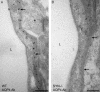

Recovery from neuronal activation requires rapid clearance of potassium ions (K+) and restoration of osmotic equilibrium. The predominant water channel protein in brain, aquaporin-4 (AQP4), is concentrated in the astrocyte end-feet membranes adjacent to blood vessels in neocortex and cerebellum by association with alpha-syntrophin protein. Although AQP4 has been implicated in the pathogenesis of brain edema, its functions in normal brain physiology are uncertain. In this study, we used immunogold electron microscopy to compare hippocampus of WT and alpha-syntrophin-null mice (alpha-Syn-/-). We found that <10% of AQP4 immunogold labeling is retained in the perivascular astrocyte end-feet membranes of the alpha-Syn-/- mice, whereas labeling of the inwardly rectifying K+ channel, Kir4.1, is largely unchanged. Activity-dependent changes in K+ clearance were studied in hippocampal slices to test whether AQP4 and K+ channels work in concert to achieve isosmotic clearance of K+ after neuronal activation. Microelectrode recordings of extracellular K+ ([K+]o) from the target zones of Schaffer collaterals and perforant path were obtained after 5-, 10-, and 20-Hz orthodromic stimulations. K+ clearance was prolonged up to 2-fold in alpha-Syn-/- mice compared with WT mice. Furthermore, the intensity of hyperthermia-induced epileptic seizures was increased in approximately half of the alpha-Syn-/-mice. These studies lead us to propose that water flux through perivascular AQP4 is needed to sustain efficient removal of K+ after neuronal activation.